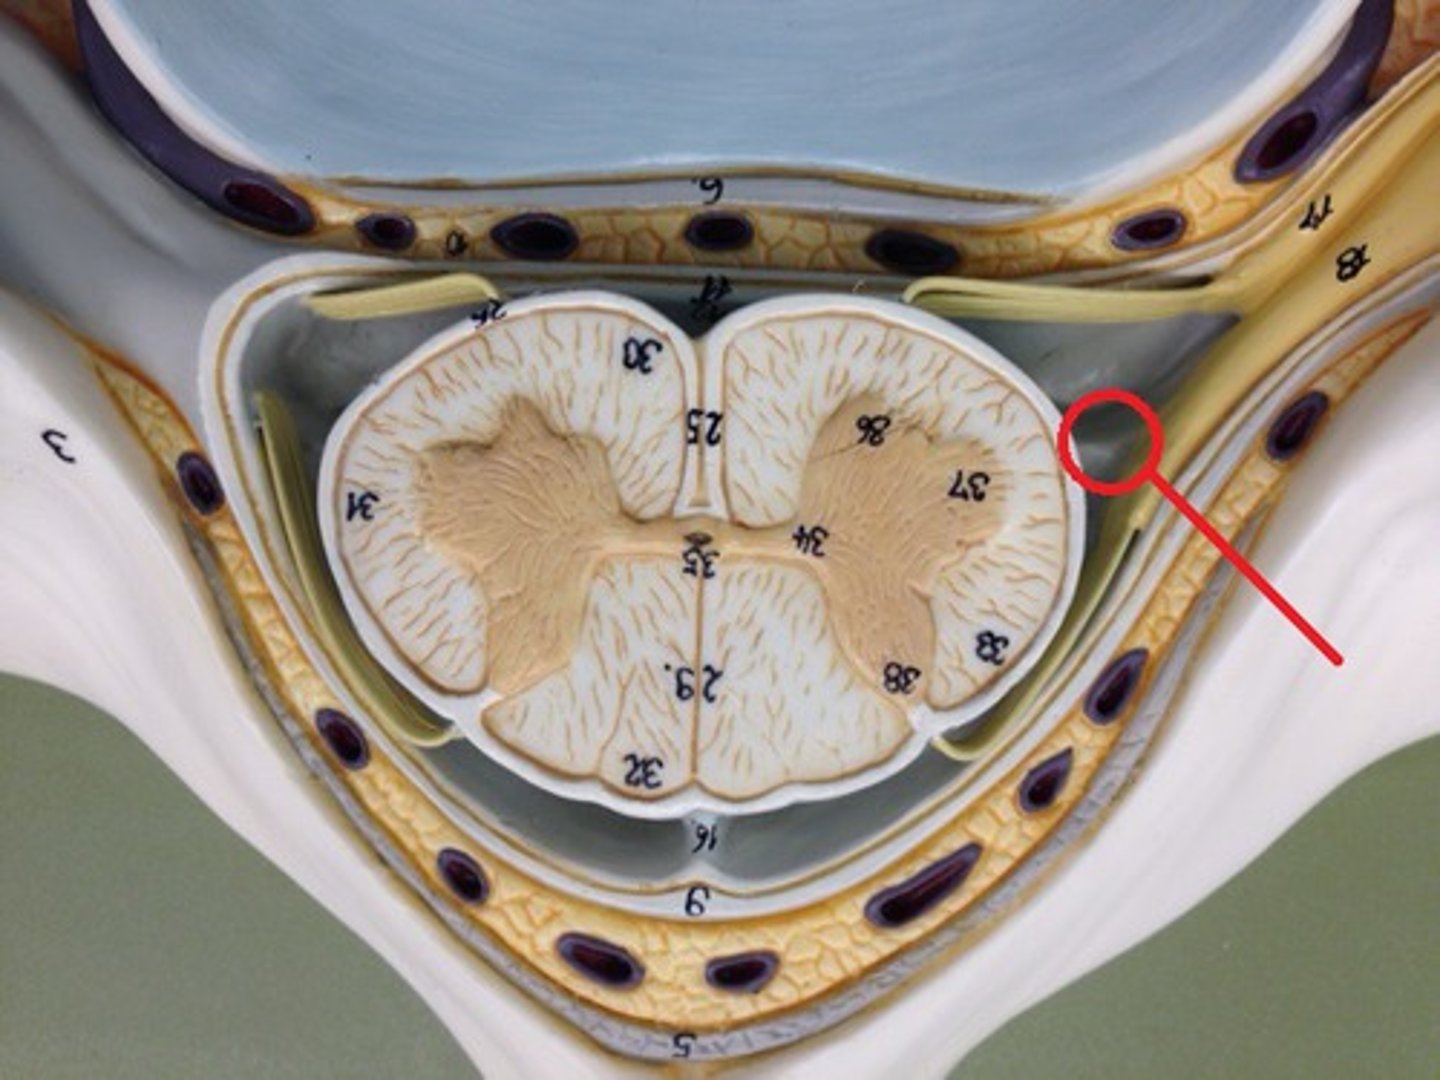

spinal meninges

3 specialized membranes surrounding spinal cord and brain

Stability, shock absorption, carry blood supply (oxygen and nutrients)

3 spinal meninges (Superficial to deep)

dura mater, arachnoid mater, pia mater

Dura mater

arachnoid mater

Pia mater

subarachnoid space

between arachnoid mater and pia mater

filled with cerebrospinal fluid

shock absorber; diffusion of gases, nutrients, etc.

blood vessels for spinal cord

epidural space

denticulate ligaments

pia mater, through the arachnoid mater, to dura mater

Prevents lateral movement